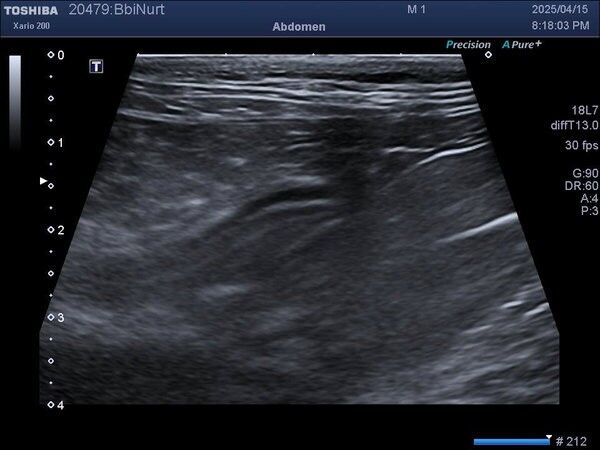

IBD는 증상만으로 확진이 어렵기 때문에, 분변검사, 혈액검사, 복부초음파, 필요시 내시경 조직검사 까지 단계적으로 진행합니다.